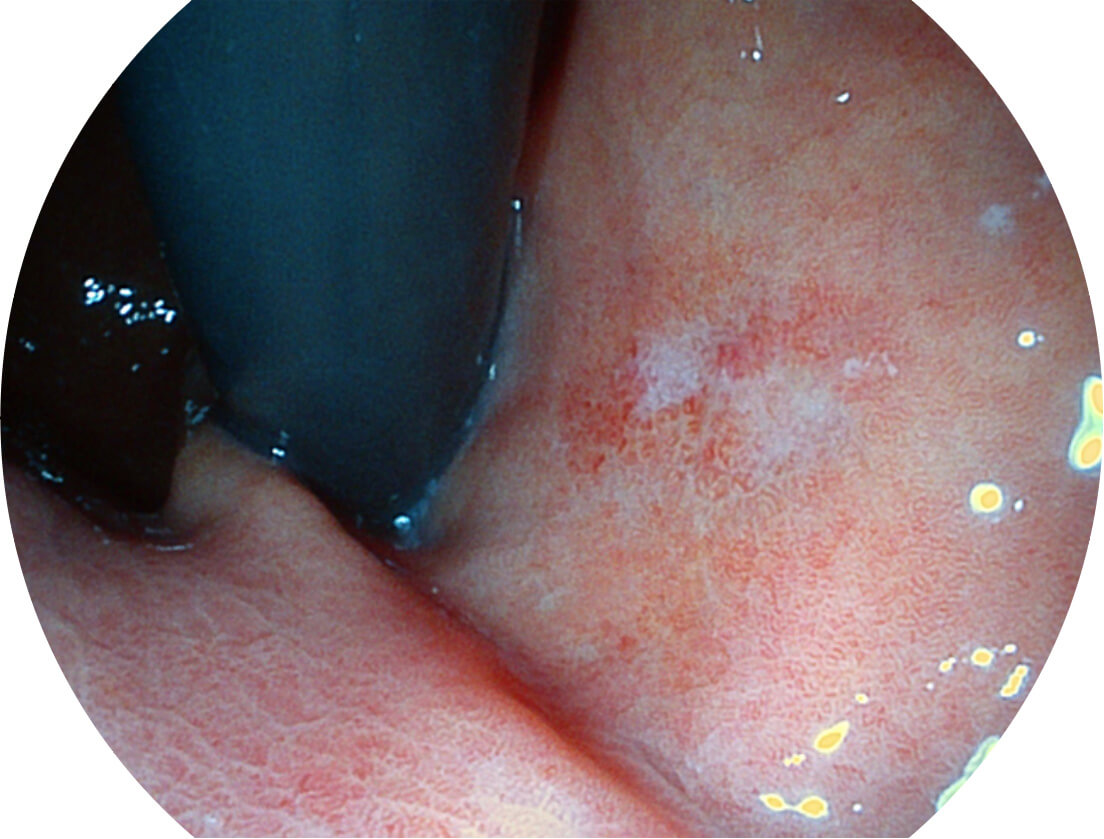

图像具有高亮度、高黏膜血管颜色对比度的特点,且不改变粘液、食物残渣、粪便的基本颜色,可在中远景下进行观察,助力消化道早期疾病的诊断。

白光图像

SFI图像

采用光路合束技术,光谱自由度高,实现了更丰富的照明模式,染色模式SFI及VIST,从远景到近景,助力消化道早期疾病诊断。